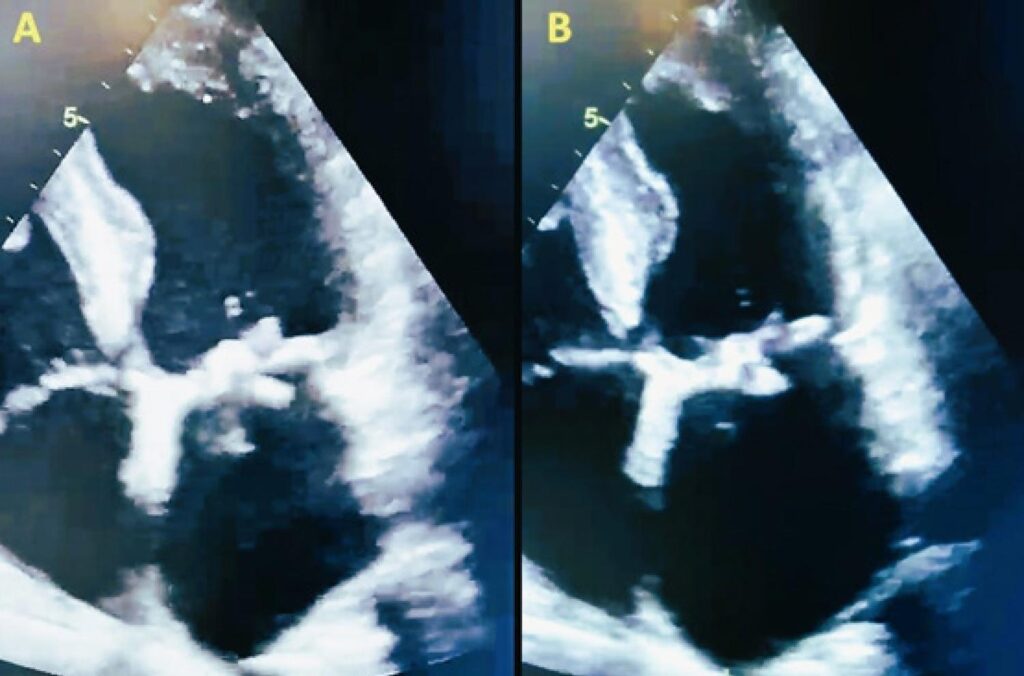

Asymptomatic Non-Bacterial Thrombotic Endocarditis Leading to a Diagnosis of Pancreatic Cancer

Non-bacterial thrombotic endocarditis (NBTE) is a phenomenon associated with sterile vegetations composed of fibrin and platelets aggregating on healthy heart valves. Most cases are diagnosed after death or in patients experiencing systemic embolization. Diagnosis relies on clinical suspicion and a compatible echocardiographic image. The correct treatment is long-term systemic anticoagulation to avoid arterial embolization, which often presents as multiple and recurrent ischemic strokes.

The first antemortem report of NBTE as the initial presentation of underlying pancreatic cancer was published in 2008. However, incidental diagnosis of uncomplicated NBTE that leads to a subsequent discovery of carcinoma is rare.